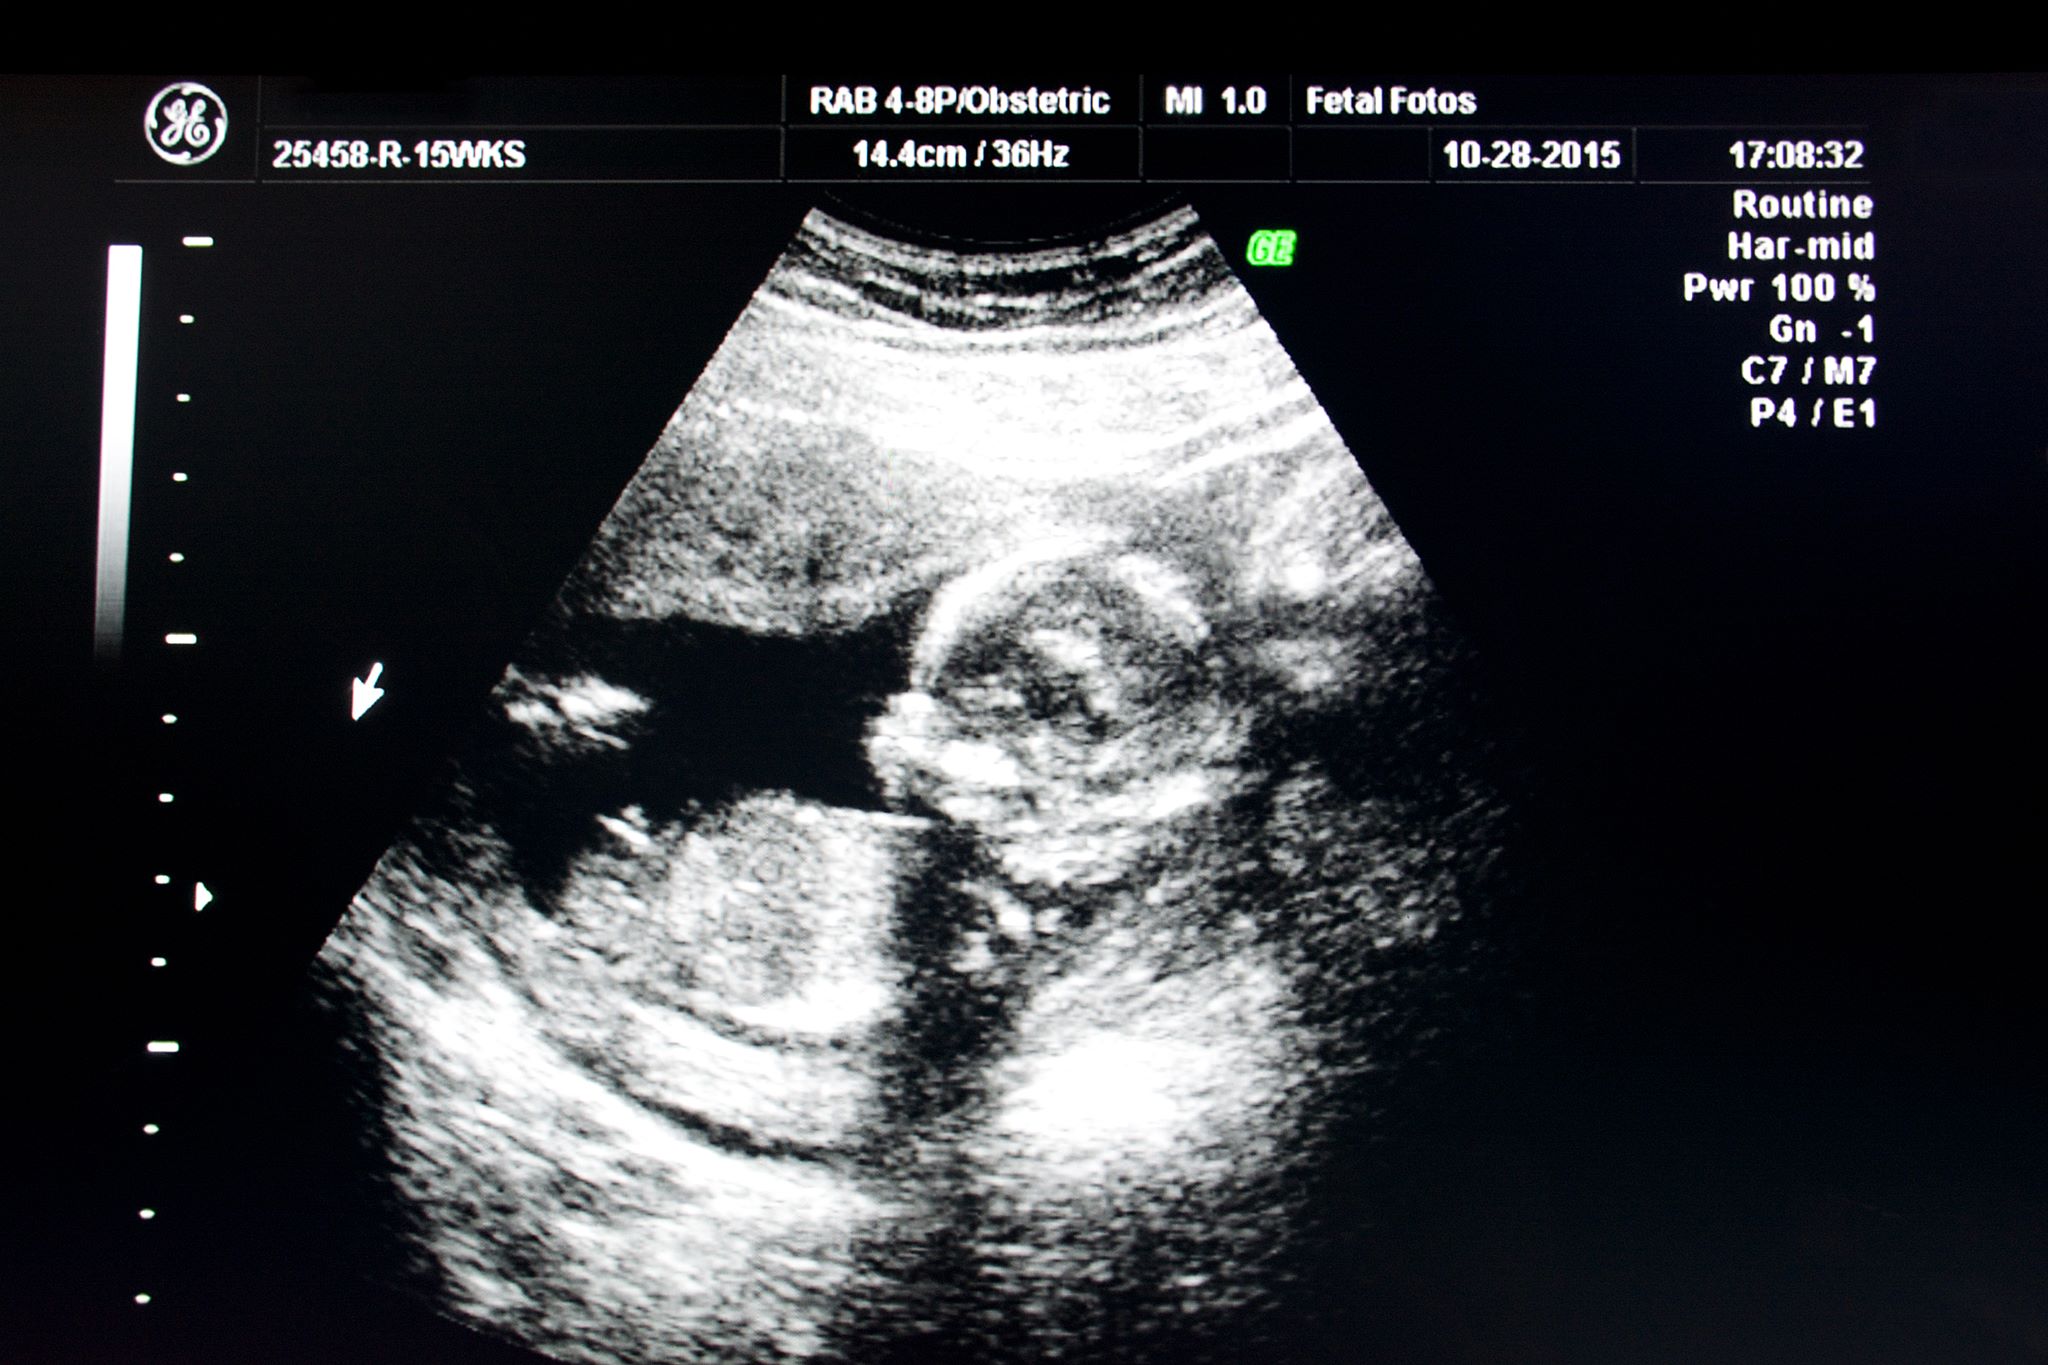

In the one diagram, the leg is extended, outlined in green. I think I see a pelvic region or a line, along with a boy nub sticking out above the leg. This is outlined in blue and the yellow is umbilical cord.

In the diagram where the leg is not extended, I believe to see a developing scrotum, outlined in red, with male nub sticking out and stacked right on it yellow.